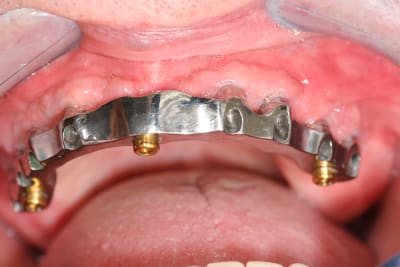

J'ai placé ces piliers locator (biomet) en juin 2012, j'ai dû les changer aujourd'hui à cause de l'usure du métal.

L'usure est également répartie sur toute la périphérie des deux piliers, une usure partielle pourrait faire penser à un problème de parallélisme , mais ce n'est pas le cas ici.

L'usure peut surtout provenir d'un mauvais équilibrage entre les parties femelles. Tes parties femelles sont placées par toi ou ton prothésiste ?

Dans ce cas c'était par moi au fauteuil